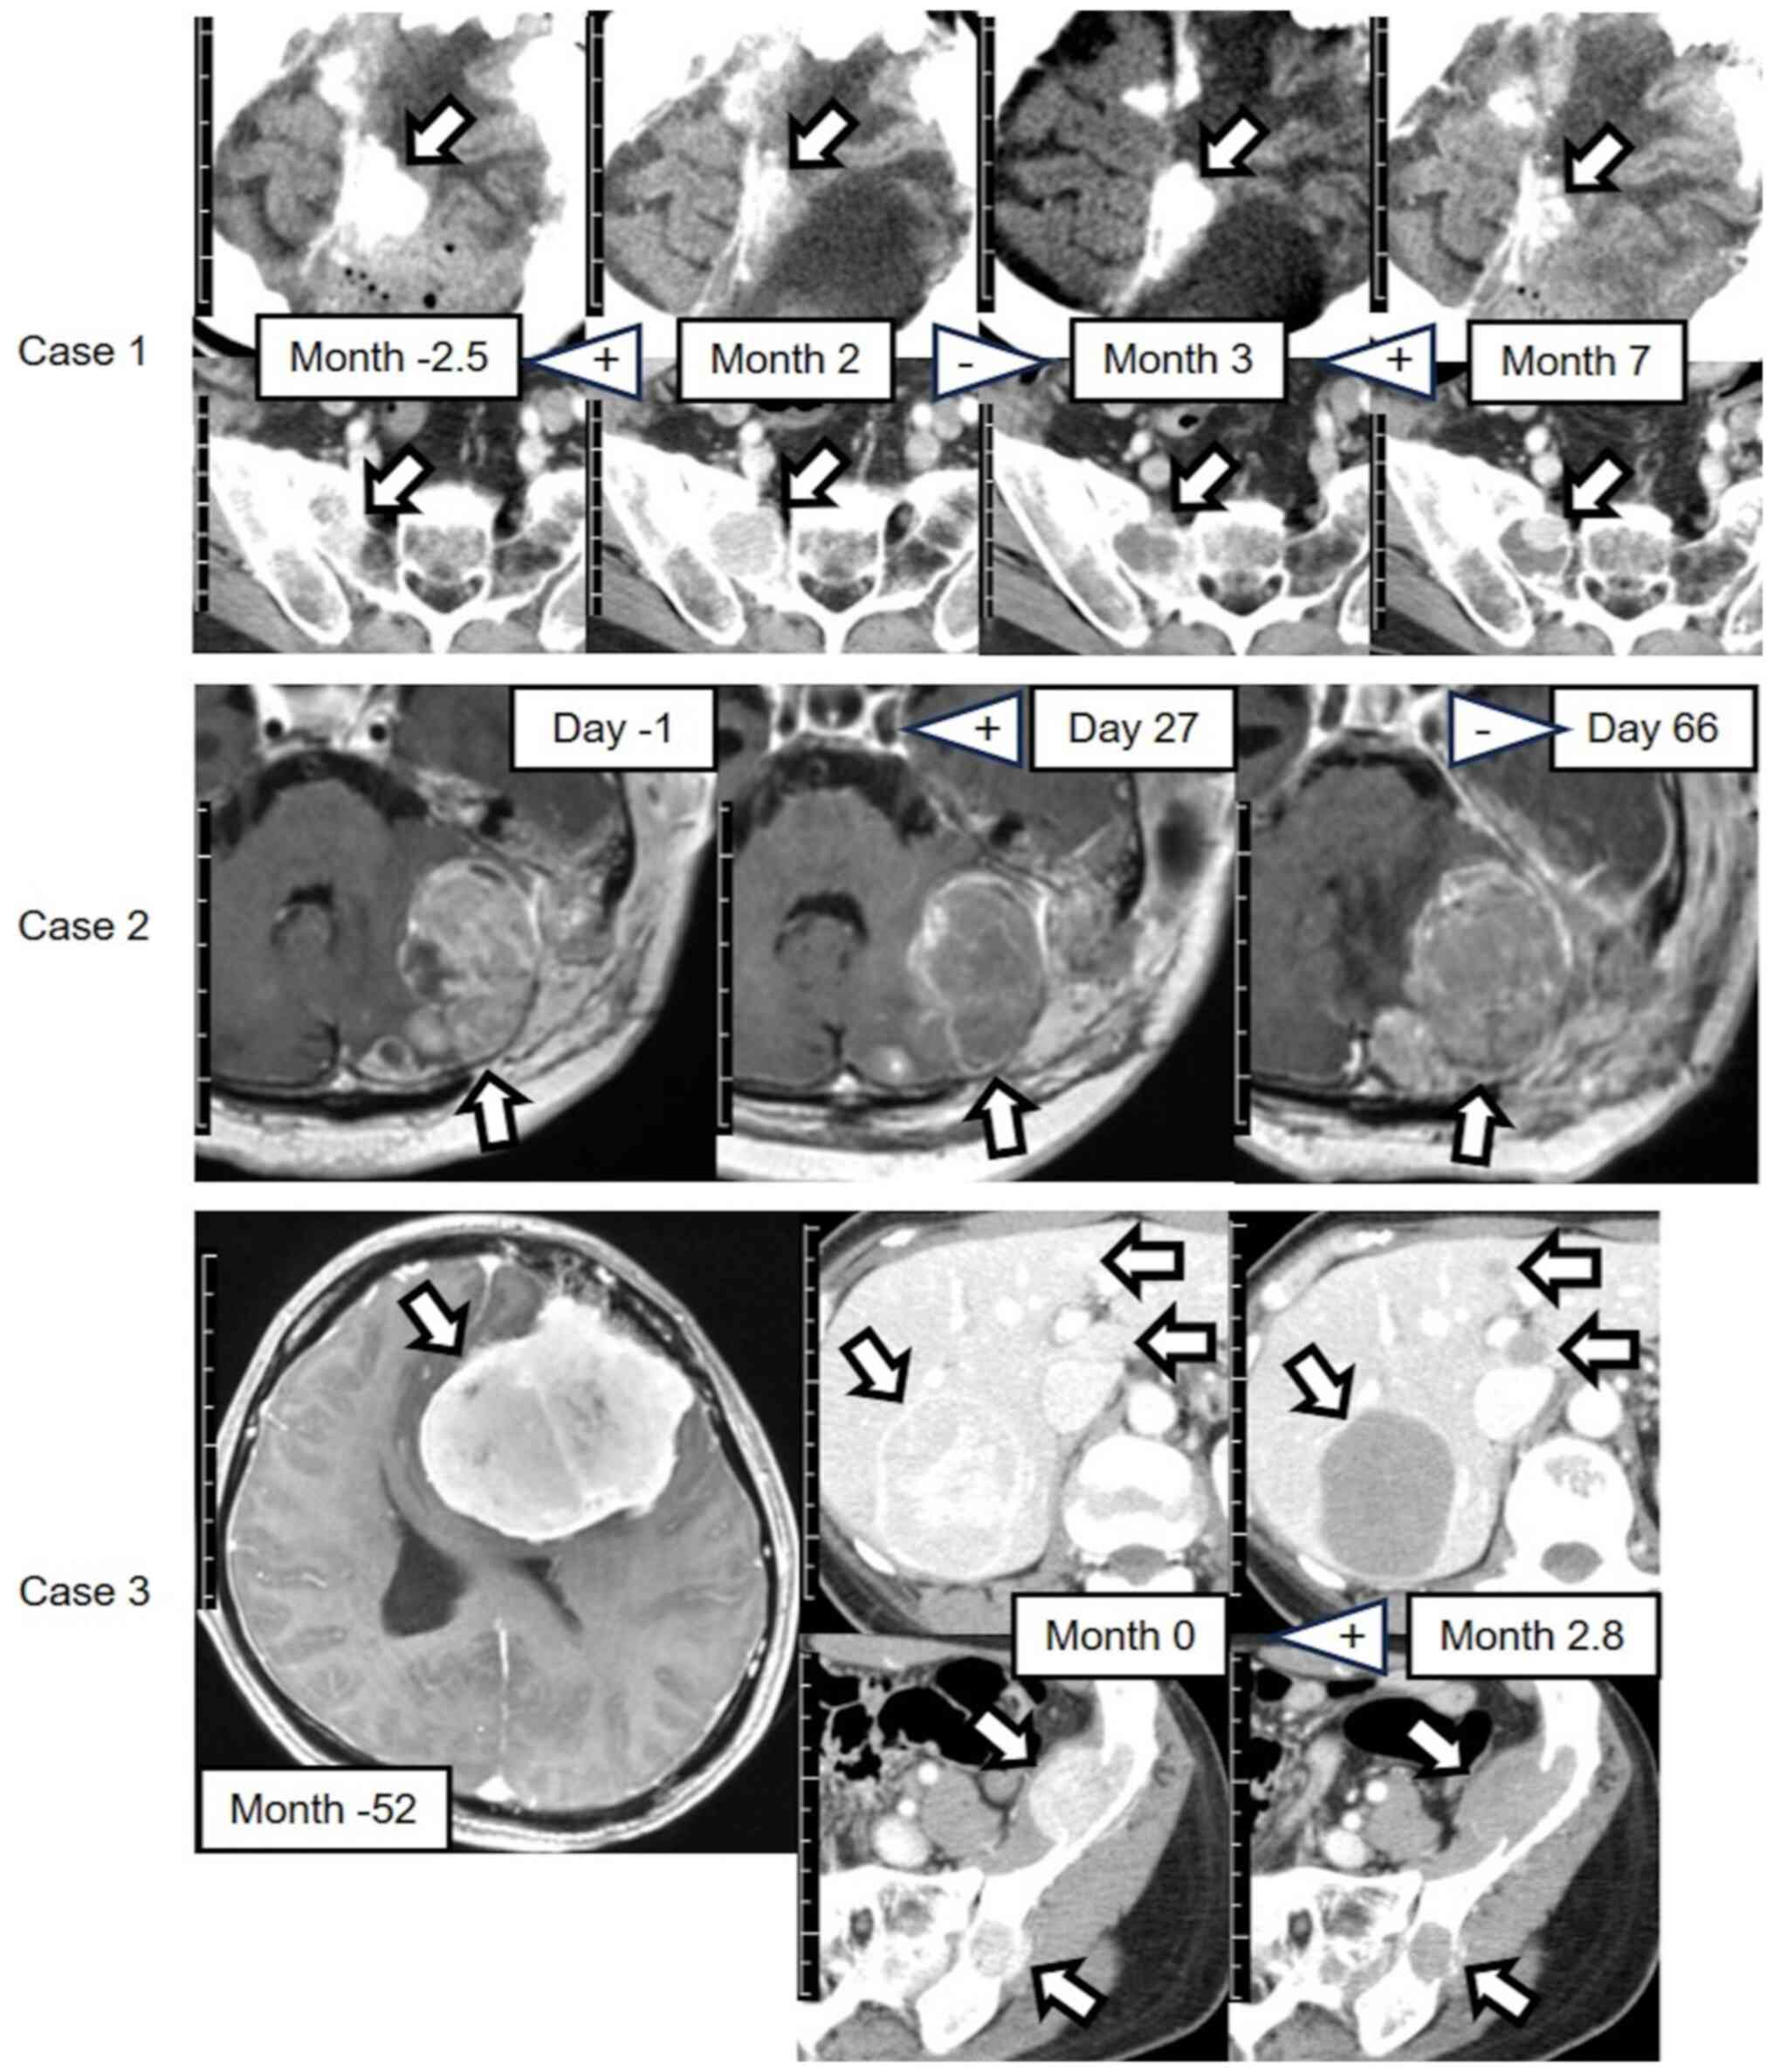

Central nervous system (CNS) solitary fibrous tumors (SFTs) are rare but aggressive, often metastasizing to extracranial regions, with no established treatments apart from surgery. Pazopanib, a multikinase angiogenesis inhibitor, is used to treat extracranial SFTs; however, its efficacy for treating CNS SFTs remains unclear. To address this issue, the efficacy of pazopanib was investigated, focusing on tumor density and size in CNS SFTs with extracranial metastases after initiation, interruption or resumption of pazopanib treatment. The present study retrospectively reviewed 3 consecutive cases of CNS SFTs showing extracranial metastases that were referred to Kochi Health Sciences Center (Kochi, Japan) between January 2018 and April 2024 and were treated with pazopanib. All measurable lesions observed via contrast‑enhanced computed tomography (CT; 50 lesions) and magnetic resonance imaging (MRI; 21 lesions) were evaluated. Cases 2 and 3, meeting the Choi criteria, showed stable disease and achieved partial response after pazopanib initiation, respectively. In Case 1, both intracranial and extracranial tumor CT densities decreased after initiation and resumption of pazopanib treatment. However, both tumor CT sizes increased after interruption of pazopanib treatment. In Case 2, MRI revealed decreases and increases in the intracranial tumor size after initiation and interruption, respectively. Notably, pazopanib interruption caused rapid infratentorial tumor growth and death. Case 3 showed decreased extracranial tumor CT densities and sizes after pazopanib initiation, with pazopanib administered for 3.5 years. Thus, pazopanib may offer the potential to control both intracranial and extracranial tumors in patients with CNS SFTs with extracranial metastasis; however, treatment interruption requires careful consideration.